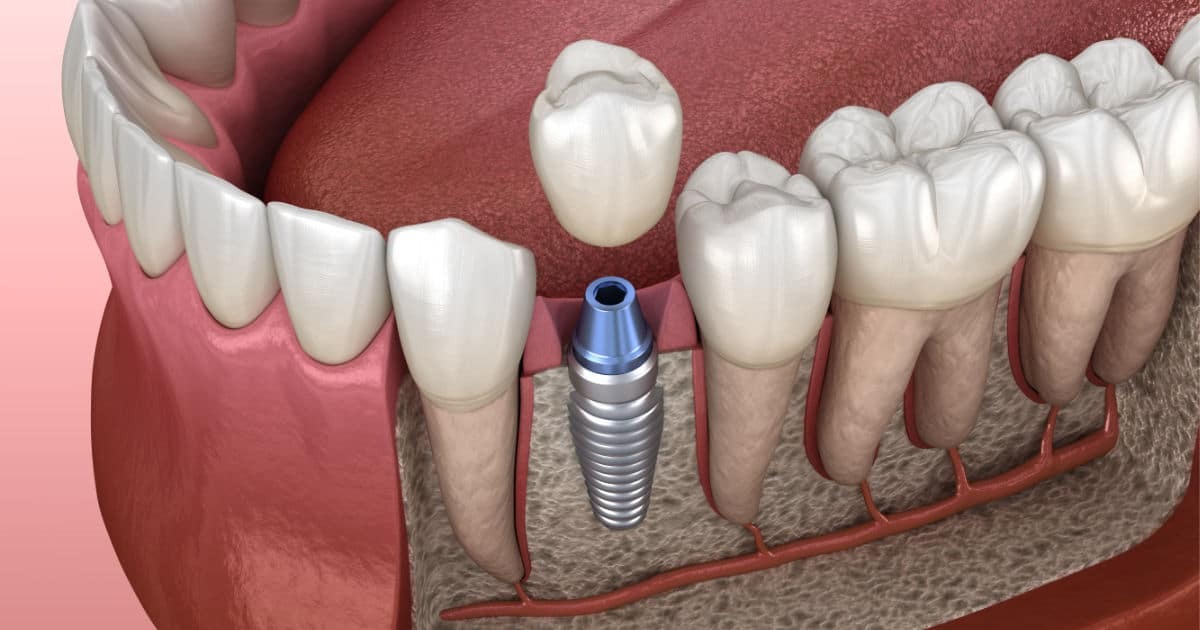

Dr. Jairo Chavez Diaz

- Implantes y Endodoncia